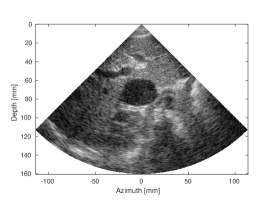

| (a) SLT | (b) MLT, (Tukey, =0.5) | (c) MLT, CNN | |

| CNR=2.33, CR=-29.33dB | CNR=1.69, CR=-19.16dB | CNR=2.2, CR= -29.24dB | |